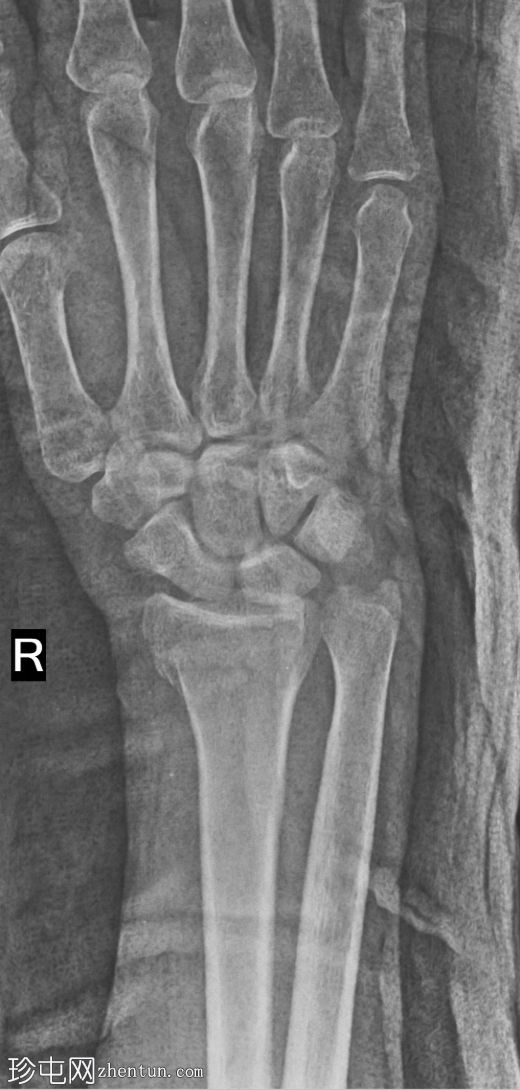

正位片

桡骨远端骨折,远端骨折块轻微掌侧移位

正位片未见明显的关节内台阶